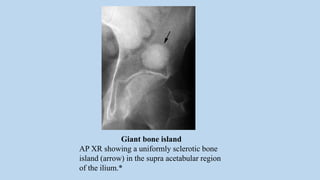

Giant bone island

AP XR showing a uniformly sclerotic bone

island (arrow) in the supra acetabular region

of the ilium.*